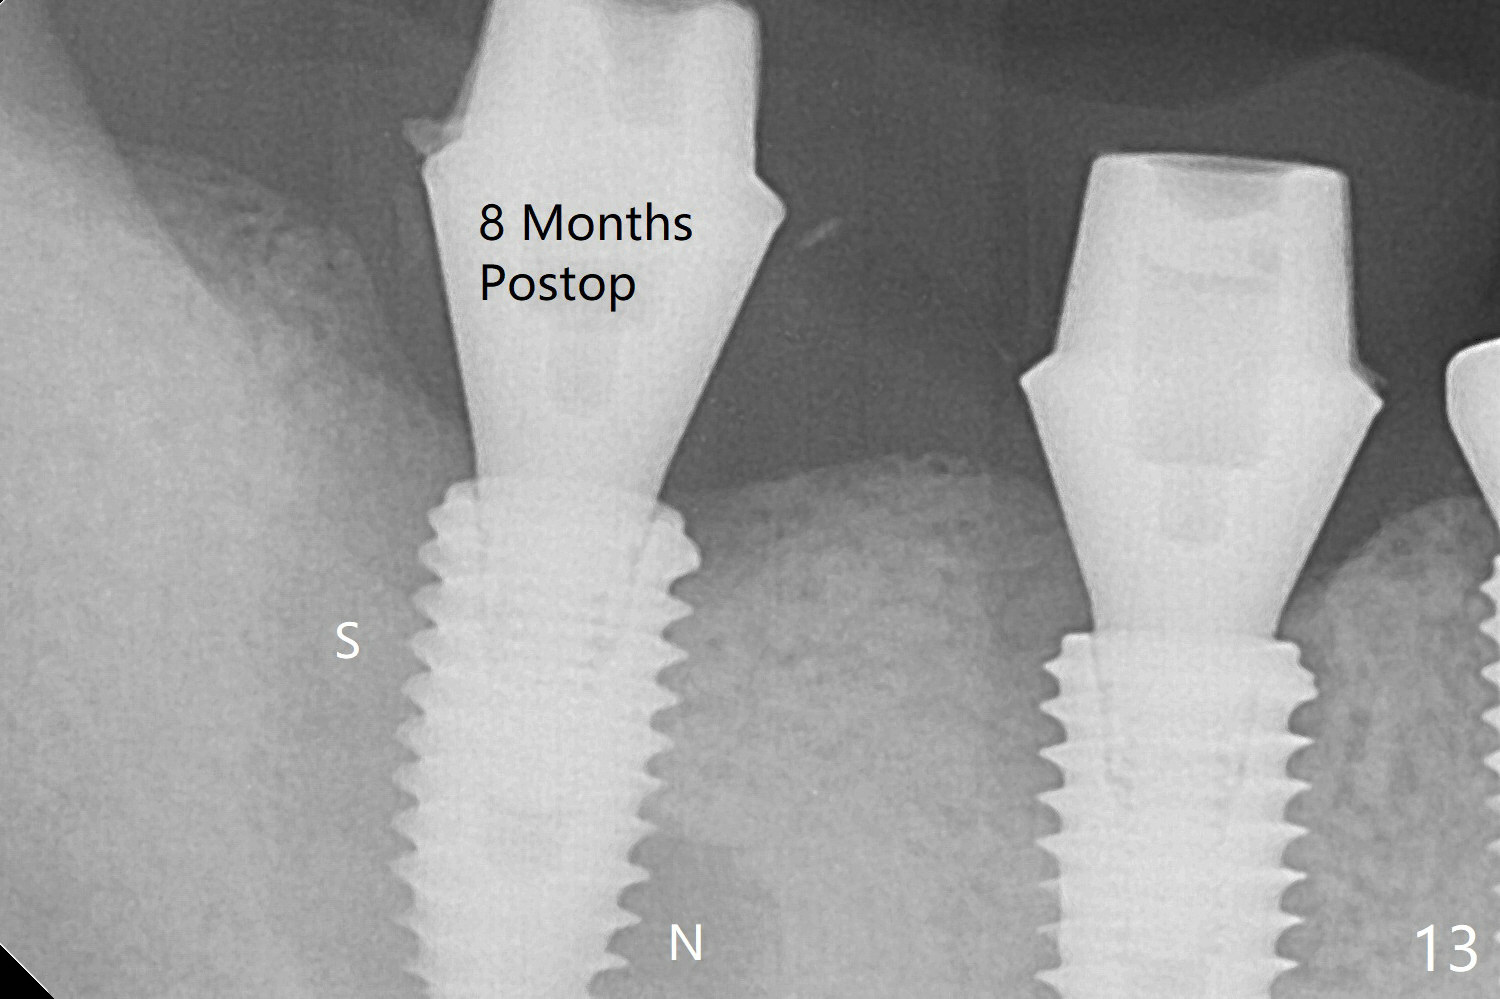

The bone at #30 and 31 is so hard that plenty of bone shaving is saved as bone graft to be placed in the socket of #31 (Fig.2 *). More graft is placed after placement of a healing abutment. No provisional is fabricated because of limited vertical space. The patient is hesitant about apicoectomy. After discussion of advantages and disadvantages of the latter vs. extraction and implant, the patient chooses the extraction. The latter turns out to be smooth with socket preservation (Fig.5, 6 *). Immediately postop PA shows bone loss at #30 and minor degree around the apex of #31 implant (Fig.4 <), which is related with hard bone and bone necrosis due to heat. The bone loss around the implants at #30 and 31 persists 3.5 month postop, while the socket heals at #29 two months post socket preservation (Fig.9). When the healing abutments with heavy plaque (similar to that in Fig.7) are removed, there is granulation tissue around the gingival cuffs with tenderness. The abutments are reloaded after cleaning with OHI. Gingiva becomes inflamed at #31 when a splinted provisional is being worn to intrude the opposing supraerupted teeth; bone resorption remains severe in the previous distal socket and the mesial necrotic area (Fig.13 S, N). Oral hygiene is bad.